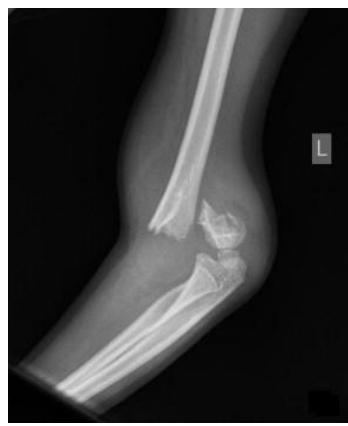

Q17: 5-year-old boy with closed injury - Treatment

A 5-year-old boy sustains an isolated, closed injury. He weighs 55 kg and is otherwise healthy. What is the best treatment option for this patient?

- Fixation and intramedullary nailing